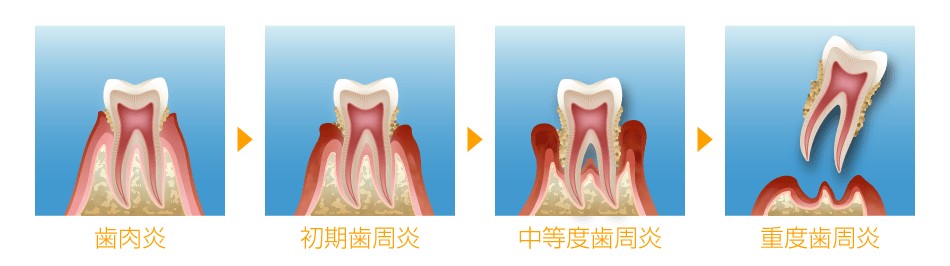

歯周病は歯垢(プラーク)に含まれる歯周病菌によって、歯ぐきが炎症を起こし、歯ぐきや歯を支える骨が溶けていき、重度の歯周病だと歯が抜け落ちてしまうこともある病気です。

歯周病には歯肉の炎症のみの歯肉炎と、歯肉の下にある骨が溶けてしまう歯周炎に分かれます。

主に10代以下のお子さんにみられる初期の歯肉炎では、ブラッシング指導が重要となります。おとなになる前にしっかりとした歯磨きができるようにしておくことで歯肉炎の改善とともに、成人してからの歯周炎の予防にも繋がります。

軽度の歯周炎では、ブラッシング指導とともに歯石を除去するスケーリングやSRPなどの初期治療を行います。軽度の歯周炎の段階で食い止めることで将来的な歯の喪失を防ぐことに繋がります。

重度の歯周炎となってしまうと、基本治療のみでは治癒せず、歯周外科治療が必要となることがございます。歯肉を開き、基本治療では取り切れなかった歯肉の奥深くに隠れた歯石を見える状態にすることで、歯石を一掃します。

骨がほとんど残っていないなど、進行状態によっては、歯を抜かざるをえないこともございます。

その他、失った骨を復活させる歯周組織再生療法といった治療法もございますので、気になる方はご相談ください。

歯周病は、自覚症状がないまま進行し、自覚症状が出てからだとすでに重度歯周炎となっている場合もあります。全身の健康にも影響を与えますので、定期的なクリーニングで、お口を清潔に保ち、歯周病の予防にも着目してみてはいかがでしょうか。